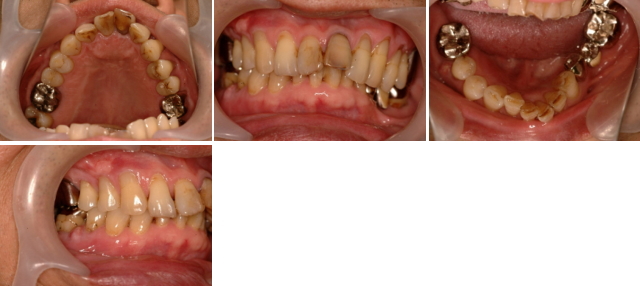

患者さんは現在70歳の男性です。

「歯肉が膿んで痛い」と来院されました。口腔内を診てみますと右下の奥歯の根が割れて歯肉が化膿していました。この部分以外の歯肉も時々腫れるそうです。無くした歯も虫歯からでなく歯周病で抜いたそうです。左側の上下の歯は、すれ違いを起こしていて噛み合っていません。専門的になりますが、前歯と奥歯はお互いに助け合っています。その関係が壊れてしまうと、奥歯に悪い力がかかり歯が割れてしまい、前歯は広がってきてしまっています。このように歯周病と噛み合わせ病が重なり、重症化してしまうことがよく起こります。歯周病の治療の中には、細菌のや歯石のコントロールの他に、歯にかかる力のコントロールをすることもあります。